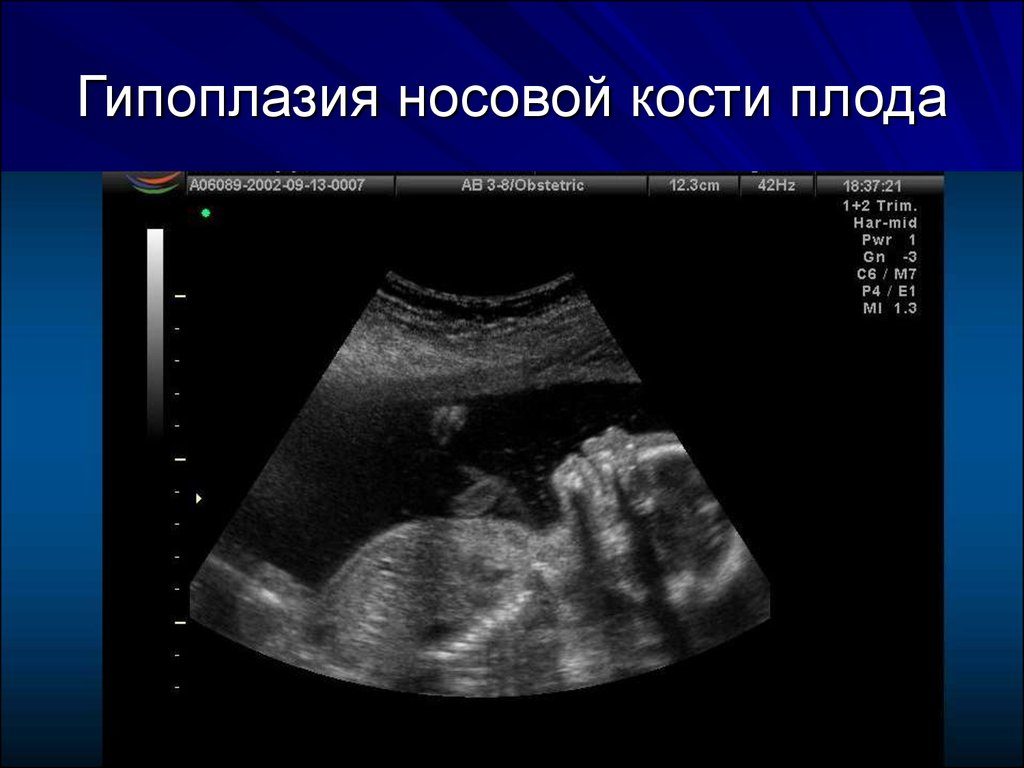

2. Гипоплазия носовой кости. УЗИ сделано на 12 неделе беременности. Длина — 1,4 мм (ниже границы нормы).